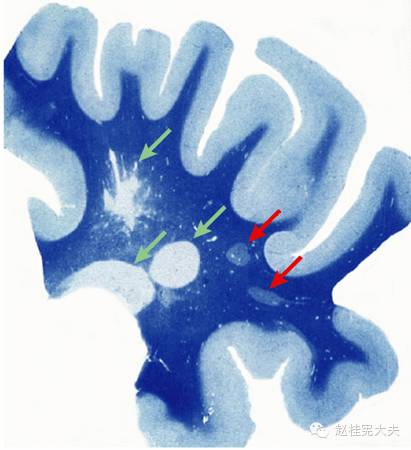

一、MS的病理特征(作者曾发文介绍过MS的病例特点,参见多发性硬化的典型病灶)

MS的急性斑块在血脑屏障破坏不久后出现,镜下见血管周围水肿、髓鞘肿胀且开始破碎,伴轻微的小胶质细胞反应,无明显淋巴细胞或巨噬细胞浸润;

早期活动阶段以明显的髓鞘崩解为特征,斑块内挤满了含有Luxol-fast blue染色的髓鞘降解产物和髓鞘蛋白的巨噬细胞,血管周围可见明显的淋巴细胞鞘,伴显著的反应性星形细胞胶质化和轴突损伤;

进入疾病慢性期,斑块内显示较多含髓鞘碎片的巨噬细胞伴周边高度活化的小胶质细胞,仅见较少的炎性细胞浸润,且常表现为完全性脱髓鞘和不同程度的轴突减少。

至慢性非活动期,斑块显示较少的炎性反应,小胶质细胞和巨噬细胞罕见,斑块逐步向纤维性星形细胞胶质“瘢痕”演化,轴突密度大大减少。

脱髓鞘斑块可自发修复为“影子”斑块,因少突细胞及其祖细胞增多而显示斑块内细胞结构的增加,Luxol-fast blue染色可使其轻微着色,在疾病早期髓鞘几乎可完全性再生,在晚期活动性及慢性病变的边缘可见髓鞘部分性再生区。